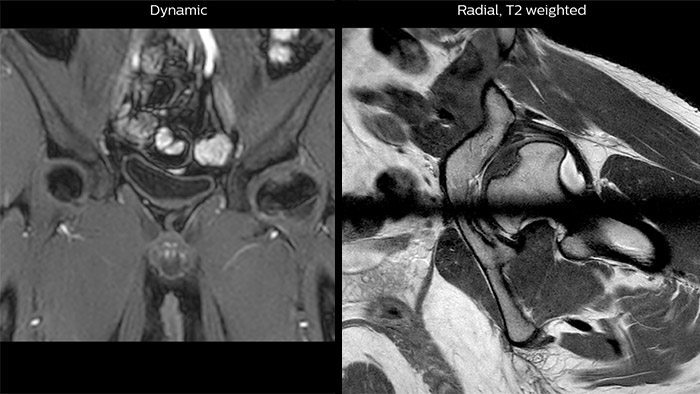

Perthes disease in left hip

The affected area on the upper circumference of the left hip shows contrast uptake in the dynamic scan. The radial scan nicely depicts the hip area, despite the dark shape in the center that is inherent to the radial way of scanning.